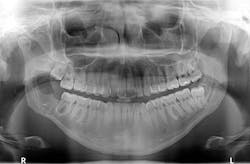

Bone has filled in, no paresthesia is present, and there are no recurrent lesions or abnormal cell formation. No. 17 will be monitored closely with plans for removal when the bone on the right side has healed sufficiently. Three-month (figure 4) and six-month (figure 5) radiographs are shown below.